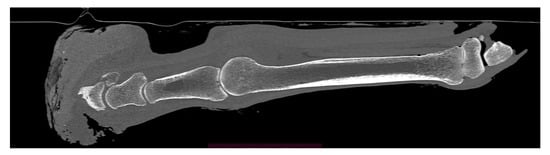

Case Presentation